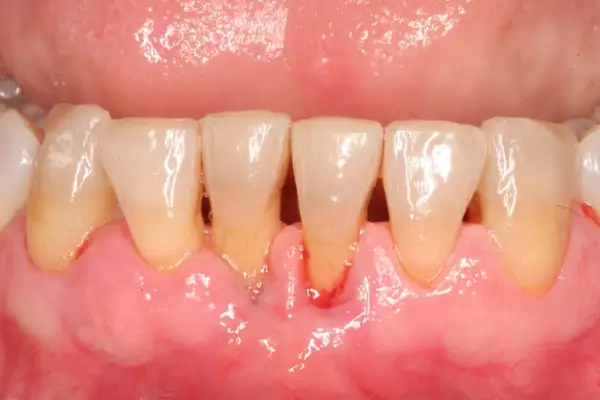

Первые признаки воспаления дёсен

Ранние симптомы легко упустить, особенно если они не сопровождаются болью. Однако именно на этом этапе лечение максимально эффективно.

Обратить внимание стоит на:

- покраснение и отёчность дёсен;

- кровоточивость при чистке зубов;

- неприятный запах изо рта;

- повышенную чувствительность;

- зуд или дискомфорт.

При наличии этих признаков важно обратиться к стоматологу как можно раньше.

Чем опасно запущенное воспаление

Без своевременного вмешательства гингивит (начальная стадия воспаления) может перейти в пародонтит — более серьёзную форму, при которой разрушается связочный аппарат зуба. Последствия могут быть необратимыми:

- образование пародонтальных карманов;

- подвижность зубов;

- разрушение костной ткани;

- потеря даже полностью здоровых зубов.